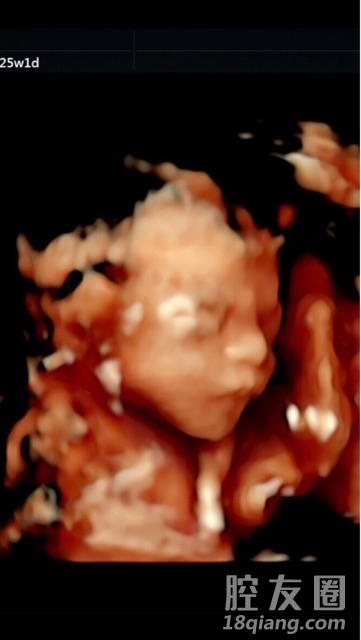

不知道为啥,最后一个半月开始越来越焦虑了~大家都是几周开始休产假的